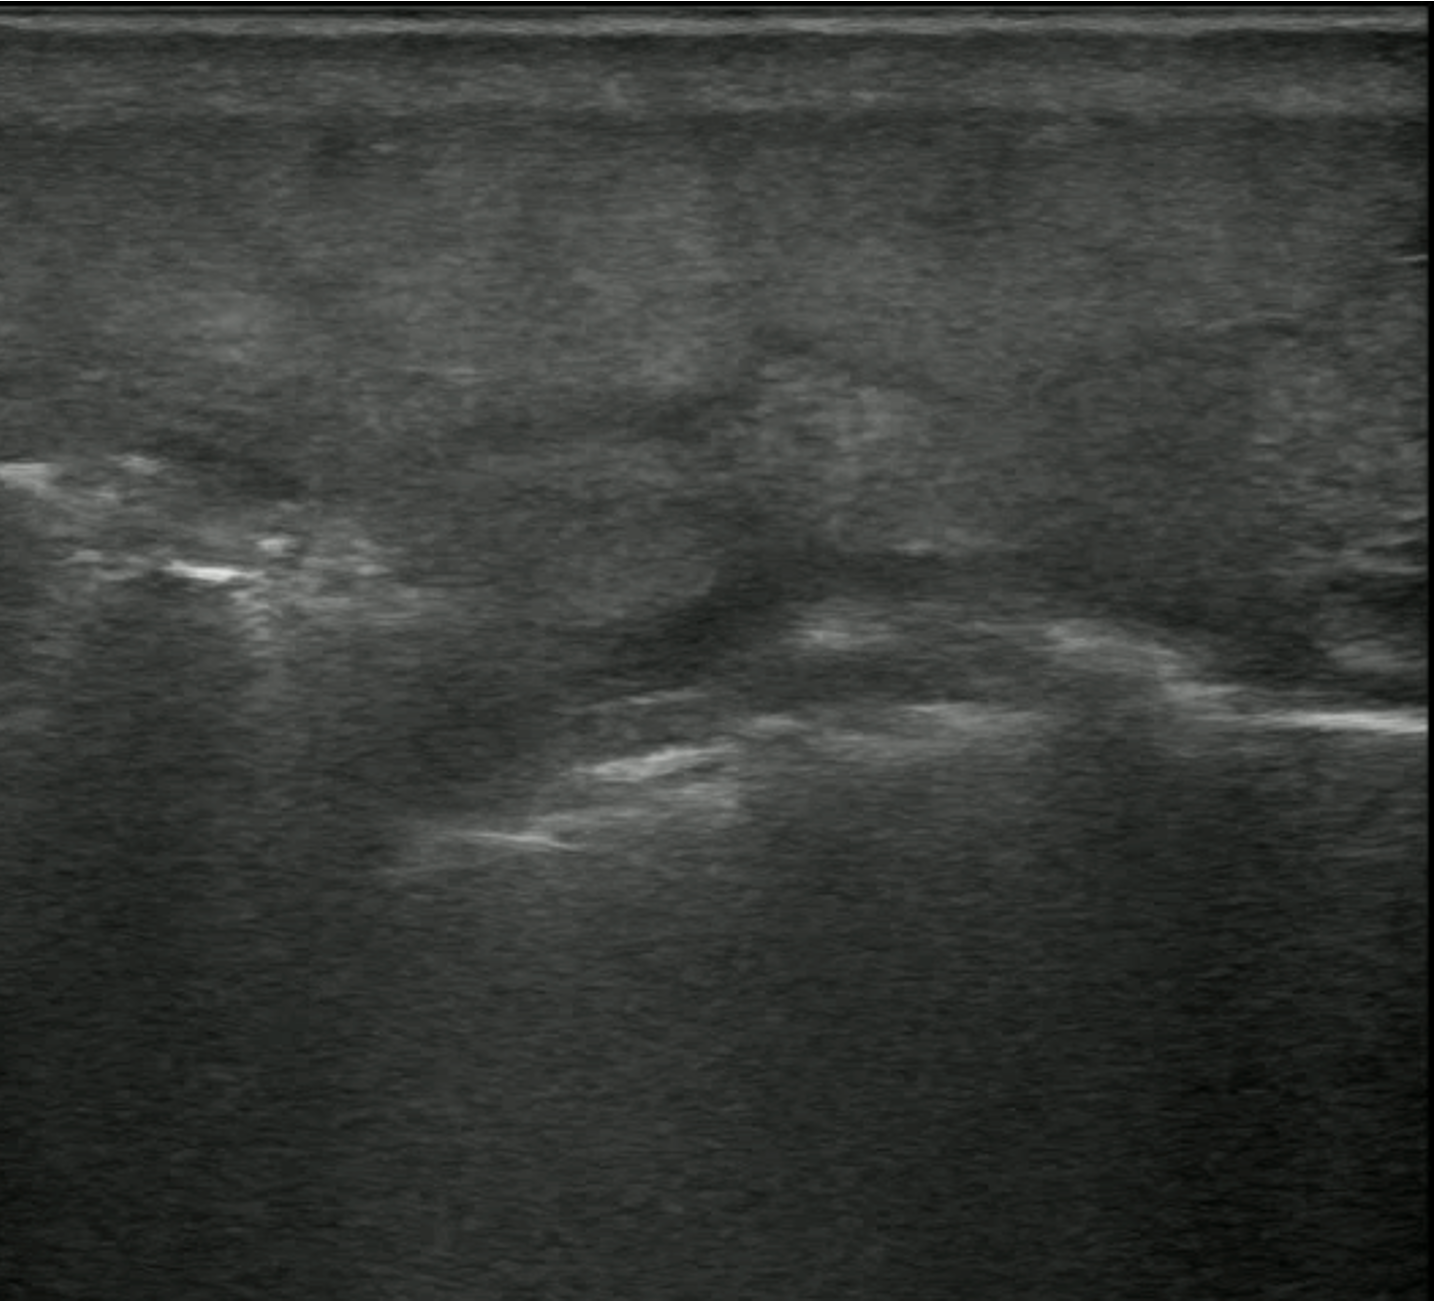

POCUS Images

• Medial Thigh Soft Tissue

POCUS Interpretation

• Cobblestoning: Fat lobules separated by hypoechoic fluid (Blue arrows)

• Seen in any cause of tissue edema

cobbllstoning

• Hyperechoic lines (Red Arrow) with dirty white shadowing (Green Arrows)

• This Finding is suggestive of gas within the Soft Tissues

hyperechoiclines

• Fluid Stripe along Fascial Plane

fluid stripe